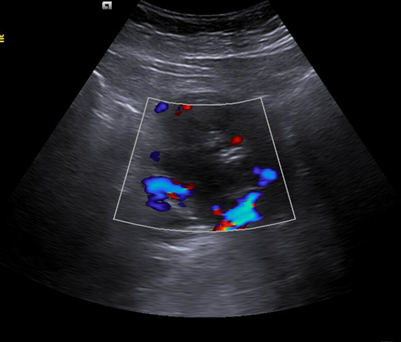

Hallazgos ecográficos

Riñón derecho 9,9 cm con morfología y ecogenicidad conservada. Presenta hidronefrosis grado III. No se identifica causa obstructiva.